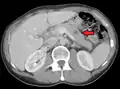

Main sites of metastases for some common cancer types. Primary cancers are denoted by "...cancer" and their main metastasis sites are denoted by "...metastases".[28]

There is a propensity for certain tumors to seed in particular organs. This was first discussed as the "seed and soil" theory by Stephen Paget in 1889.[29] The propensity for a metastatic cell to spread to a particular organ is termed 'organotropism'. For example, prostate cancer usually metastasizes to the bones. In a similar manner, colon cancer has a tendency to metastasize to the liver. Stomach cancer often metastasises to the ovary in women, when it is called a Krukenberg tumor.